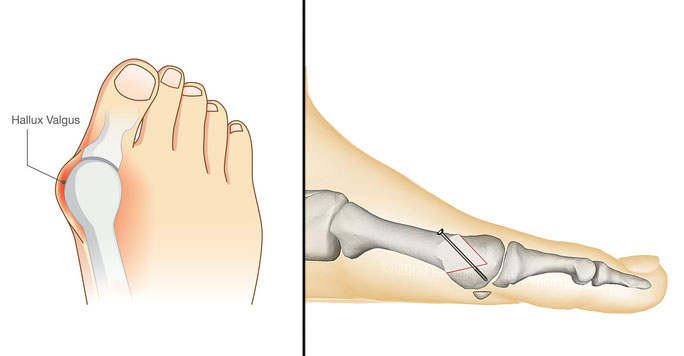

Qu’est ce qu’un hallux valgus ?

L'hallux valgus est une déviation du gros orteil, aussi appelé "oignon" entrainant une déformation de l'avant du pied. Ce défaut provoque généralement douleur et difficulté à la marche et touche plutôt les femmes. Il devient difficile de se chausser surtout lorsque la déformation devient importante.

C'est une déviation importante du gros orteil vers le deuxième orteil qui correspond à une déformation au niveau du premier métatarsien et biensûr entraine dans la plupart des cas des douleurs de chaussage.

La sévérité de l'hallux valgus dépend de l'angle de déviation et des déformations que cela entraine sur le reste du pied.